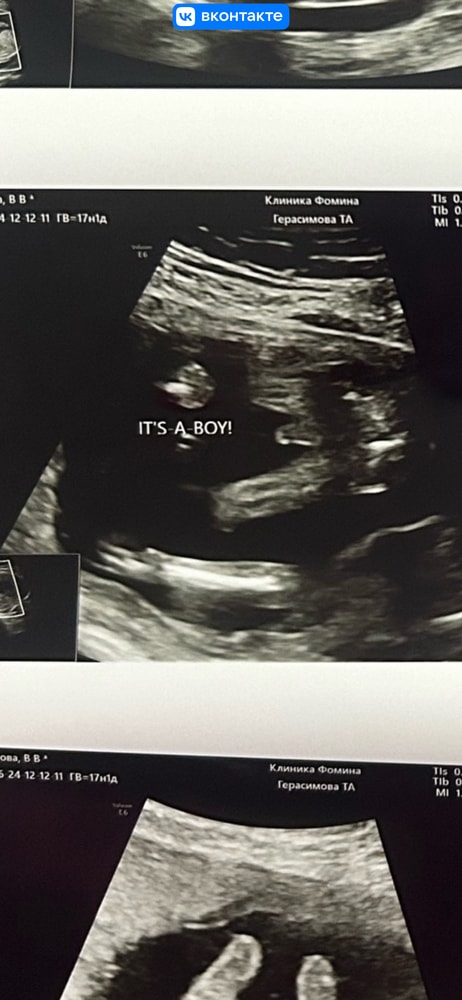

Майя , просто с 16н у моего сына было не так… Изображение Вот это мальчик без вопросов. А у вас я бы сомневалась

12.04.2025

Ну это же ещё приближено очень сильно, поэтому кажется так

Виктория, вот мой пацан) даже сомнений никаких не было,что могли с полом ошибиться. 16 недель на снимке

Мошонка и пенис вроде да. У моего старшего тоже хозяйство хорошее все сразу видно было )